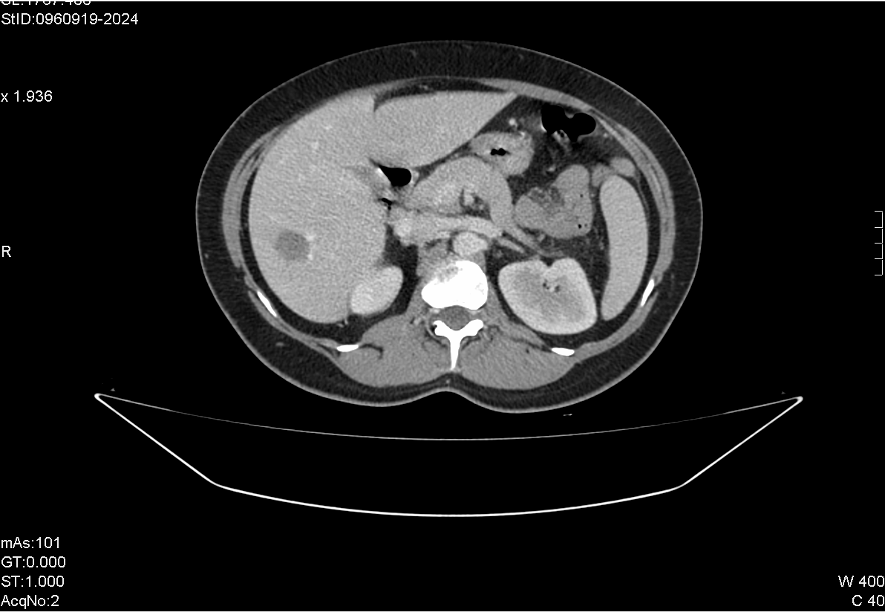

Ante la sospecha de EIP, TAC abdominal, confirma colección multiloculada en hemipelvis izquierda, en probable localización parametrial, sugestiva de absceso tubo-ovárico. Cambios inflamatorios locorregionales con leve engrosamiento de un segmento corto de sigma adyacente probablemente por contigüidad. Lesión focal hepática inespecífica, que en el contexto no permite descartar absceso secundario a embolismo séptico.

Alta con cefixima y metronidazol. Seguimiento en consultas con buena evolución. Pendiente de RMN para categorizar lesión hepática.